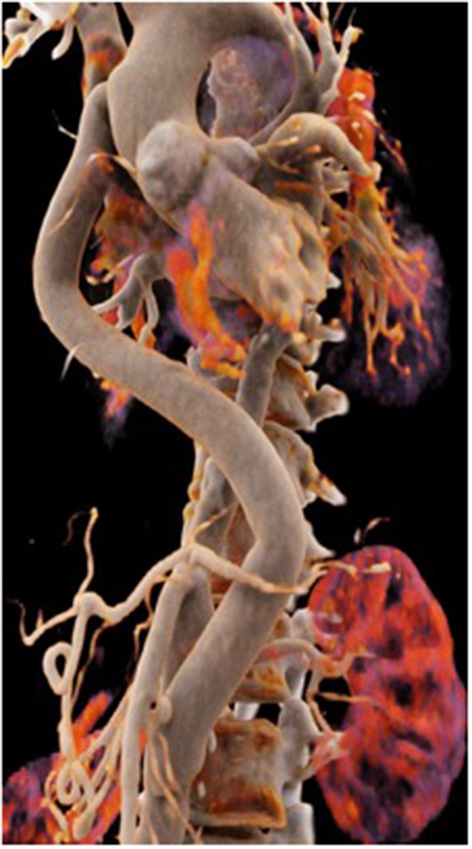

The second patient is a 45-year old female known for a Takayasu arteriitis who suffered from drug-resistant arterial hypertension, renal failure and symptoms of claudication Fontaine stage IIb-III with a walking distance of <100 m and sometimes pains at rest. She presented with a localized severe calcific stenosis of the descending aorta with a resting lumen of 3–4 mm at the narrowest site (Figure 13 both right). She was originally referred for evaluation of an endovascular approach but the interventional radiologist denied this possibility. Finally, she received an extra-anatomic ascending-to-infrarenal aortic bypass. A 16 mm vascular graft was anastomosed on the beating heart at the right lateral level of the tangentially clamped ascending aorta. The graft was then brought to the right close to the right atrium and passed through the diaphragm, then through the bursa omentalis to the retroperitoneum and the infrarenal aorta where the distal anastomosis was constructed approximatively 4–5 cm above the aorto-iliac bifurcation. Postoperative course was uneventful and symptoms as well as the arterial hypertension greatly improved soon after surgery. CT-scan demonstrated the correct position of the extra-anatomic graft (Figure 14).

Figure 14

Postoperative 3-D reconstruction of the CT-angio following ascending to infrarenal bypass in the patient with very calcified and narrowed descending aorta following Takayasu disease.